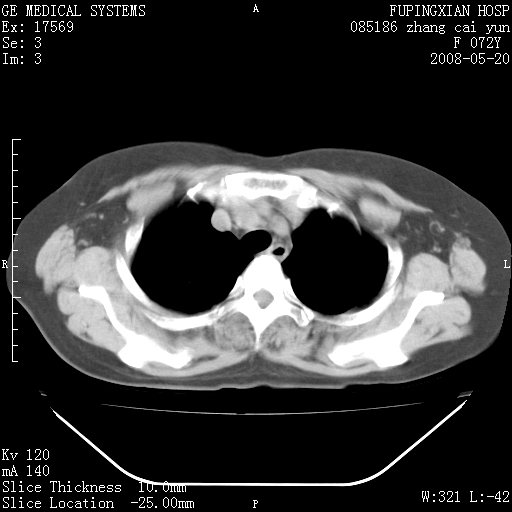

标题: CT13542:发热,咳嗽数日,经抗菌素治疗好转,请大家看排除 [打印本页]

标题: CT13542:发热,咳嗽数日,经抗菌素治疗好转,请大家看排除

右上叶支气管走行自然,未见明显管壁增厚等征像,另左主支气管起始部可见异常腔道向左侧延展左肺动脉干后方,与左下叶支气管相通,为左下叶支气管变异?

有节段性阻塞性肺炎与不张,近段支气管狭窄,周围散在肿大淋巴结影,以周围型肺癌可能性大,建议纤支镜检查。

建议纤支镜检查,考虑支气管内膜结核可能性大